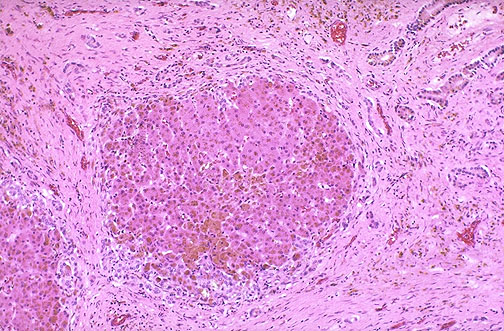

At low magnification, the small nodules of hepatocytes with surrounding fibrosis indicate cirrhosis is present. Note the markedly increased amounts of light brown hemosiderin deposits.